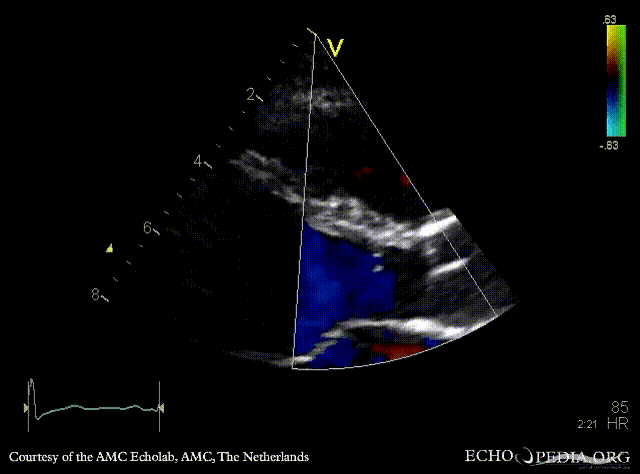

Subvalvular membrane

PSAX with Color Doppler: high velocity flow in LVOT A3CH: subvalvular membrane